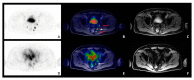

The aim of the present study is to investigate the synergic role of 68Ga-PSMA PET/MRI and 68Ga-DOTA-RM2 PET/MRI in prostate cancer (PCa) staging. We present pilot data on twenty-two patients with biopsy-proven PCa that underwent 68Ga-PSMA PET/MRI for staging purposes, with 19/22 also undergoing 68Gaa-DOTA-RM2 PET/MRI. TNM classification based on image findings was performed and quantitative imaging parameters were collected for each scan. Furthermore, twelve patients underwent radical prostatectomy with the availability of histological data that were used as the gold standard to validate intraprostatic findings. A DICE score between regions of interest manually segmented on the primary tumour on 68Ga-PSMA PET, 68Ga-DOTA-RM2 PET and on T2 MRI was computed. All imaging modalities detected the primary PCa in 18/19 patients, with 68Ga-DOTA-RM2 PET not detecting any lesion in 1/19 patients. In the remaining patients, 68Ga-PSMA and MRI were concordant. Seven patients presented seminal vesicles involvement on MRI, with two of these being also detected by 68Ga-PSMA, and 68Ga-DOTA-RM2 PET being negative. Regarding extraprostatic disease, 68Ga-PSMA PET, 68Ga-DOTA-RM2 PET and MRI resulted positive in seven, four and five patients at lymph-nodal level, respectively, and at a bone level in three, zero and one patients, respectively. These preliminary results suggest the potential complementary role of 68Ga-PSMA PET, 68Ga-DOTA-RM2 PET and MRI in PCa characterization during the staging phase.